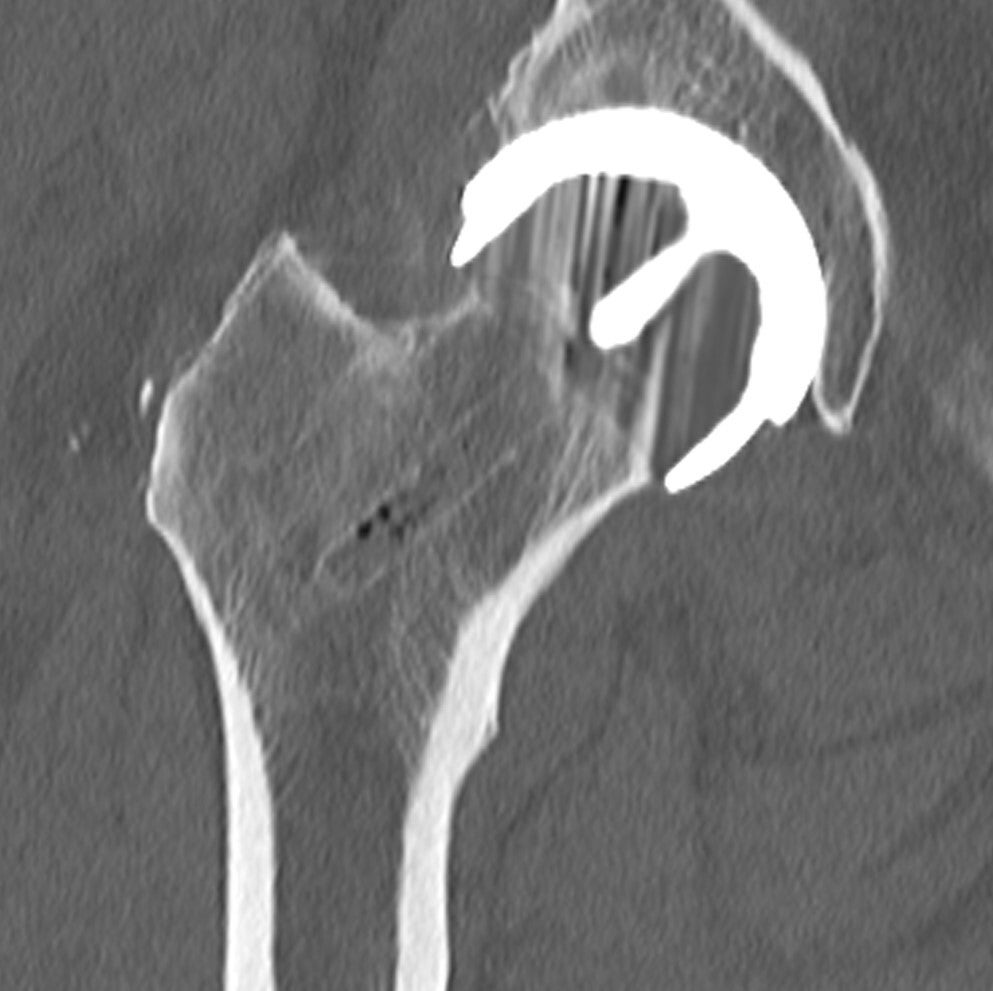

The hip is a ball-and-socket joint. During hip resurfacing surgery, the damaged surface of the ball (the head of the femur) and socket (the acetabulum in the pelvis) are carefully removed and resurfaced using smooth, durable metal components. This creates a strong metal-on-metal bearing surface.

Unlike a total hip replacement, which replaces the entire joint with a prosthesis, hip resurfacing preserves more of your natural bone. It’s especially suited to younger, active patients with good bone quality who want to maintain high levels of physical activity.

• Hip resurfacing preserves the patient’s natural femoral bone and only resurfaces the ball of the hip joint.

• Total hip replacement involves removing both the femoral head (ball) and the acetabulum (socket) and replacing them with artificial components.